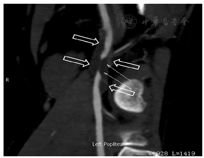

患者男,46岁,已婚。3个月前无明显诱因出现左下肢发凉、疼痛、麻木,间歇性跛行,跛行距离约100 m,休息后可缓解。无明显肿胀,皮肤无溃烂及色素沉着。既往体健,无糖尿病、高血压、脑血管病及外伤史。无饮酒、吸毒及毒物接触史。吸烟25年,平均20支/d,未戒烟。头颅CT、胸部平片、肺功能测定、血清学检测及心电图均未见异常。一般情况好,生命体征未见异常。查体:左下肢皮肤苍白,尤以膝关节以下为著,左小腿及左足皮温低,左侧股动脉搏动良好,左侧腘动脉及左侧足背动脉搏动未触及,左下肢末梢血运及感觉差。右下肢未见明显异常。生理反射存在,病理反射未引出。超声显示:左侧腘动脉走行处见长约45 mm的不规则异常回声区,挤压无明显形变,最宽处直径约12 mm,管壁不规则增厚,回声较低,其内可见不规则强回声带及不连续内膜较强回声(图1)。彩色多普勒血流显像(CDFI)示腘动脉不规则长条状血流信号,远端动脉呈小慢波。注入SonoVue造影剂后测得最窄处血流信号宽度1 mm,低回声的增厚的管壁内未见明确造影剂信号回声(图2)。超声提示:左侧腘窝所见不排除腘动脉外膜囊性病变,局部管腔不完全闭塞,建议进一步检查。随后行下肢血管CTA示左侧腘动脉管腔内见低密度充盈缺损,管腔变窄,最窄处狭窄程度约80%,狭窄长度约17.1 mm,诊断意见:左侧腘动脉低密度影,考虑血栓形成,管腔重度狭窄(图3)。患者择期手术。术中所见:左侧腘窝处可见一大小约4 cm×4 cm囊性包块,将腘动脉紧密包绕,包块近端腘动脉搏动良好,远端未见明显搏动(图4);打开囊肿外膜,可见其内充满无色透明"冻胶状"物,量约20 ml,完全清除囊肿内容物后,钝锐性结合,将囊肿从腘动脉上完整分离并切除。病理所见:破碎囊样组织,面积2 cm×1.5 cm,一侧灰白尚光滑,囊壁厚0.2~0.3 cm,另见胶冻样物。符合血管外膜囊性改变。